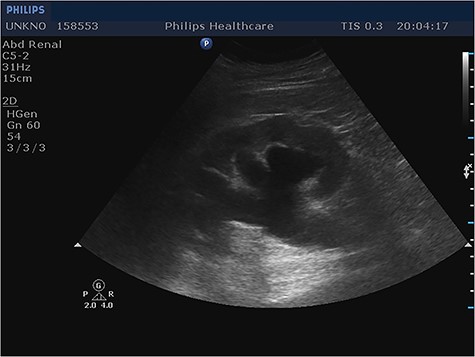

Given the fact that the patient was still hemodynamically stable, and in order to identify preoperatively the content of the incarcerated hernia sac, prompt imaging with ultrasound was considered necessary. Imaging revealed the protrusion of the entire bladder through the right internal inguinal ring and extending into the scrotum (Fig. 1), as well as hydronephrosis of the right kidney (Fig. 2), justifying the patient’s renal dysfunction.

Longitudinal ultrasound image of right kidney showed hydronephrosis. Same findings noticed in contralateral kidney (not shown).